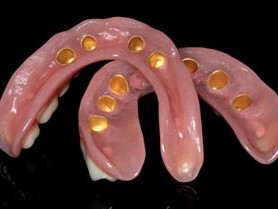

Fertigstellung der Konusprothesen

Mit entsprechenden Einbringhilfen zur exakten Ausrichtung verschraubte der Zahnarzt die individuellen Abutments mit den Implantaten und zementierte darauf die Patrizen aus Zirkonoxid. Setzt man dazu bereits die Galvanokappen auf, lassen sich die Zementüberschüsse einfacher und ohne Beschädigung der hochglanzpolierten Zirkonoxidoberflächen der Primärstruktur entfernen. Anschließend wurde das Tertiärgerüst intraoral nach dem Weigl-Protokoll im passiv fit mit den Galvanosekundärteilen verklebt. Für die folgende Ästhetikeinprobe wurden die Prothesenzähne in Wachs auf dem Gerüst aufgestellt. Das Gerüst wurde opakert und darauf die hohlgeschliffenen Prothesenzähne unter ständiger Kontrolle am Vorwall einpolymerisiert. Nach dem Finishing der Prothese konnte die Versorgung eingesetzt werden, eine okklusale Adjustierung war aufgrund der exakten Kiefer relationsbestimmung nicht notwendig (Abb. 24–30).

Die Beratungs- und Entscheidungsphase der Patientin zog sich über einen Zeitraum von annähernd zwei Jahren hin. Dieser Umstand lässt beispielhaft erkennen, dass ein implantatchirurgischer Eingriff bzw. eine implantatprothetische Versorgung einen Überzeugungsprozess mit vertrauensvoller Beratung voraussetzt. Zeit, die – wie in diesem Fall – von allen Seiten lohnenswert investiert wurde. Herausnehmbare Konusprothesen sind keinesfalls nur Arbeiten „zweiter Wahl“, denn ein festsitzender, implantatgetragener Zahnersatz ist nicht in jedem Fall realisierbar. Die Gründe hierfür können in der klinischen Situation oder in der anamnestischen Gesamtkonstitution des Patienten liegen. Vor allem umfangreiche Resorptionen der oralen Hart und Weichgewebe machen herausnehmbare Lösungen unverzichtbar, wenn augmentative Maßnahmen nicht gewünscht sind. In solchen Fällen ist eine Konusprothese eine dankbare Alternative. Hygienefreundlichkeit und unkomplizierte sowie kostengünstige Reparaturen sind weitere Vorzüge der Konusprothese, die besonders von älteren Patienten sehr geschätzt werden, ein Aspekt, der bei der aktuellen Bevölkerungsentwicklung immer wichtiger werden wird.